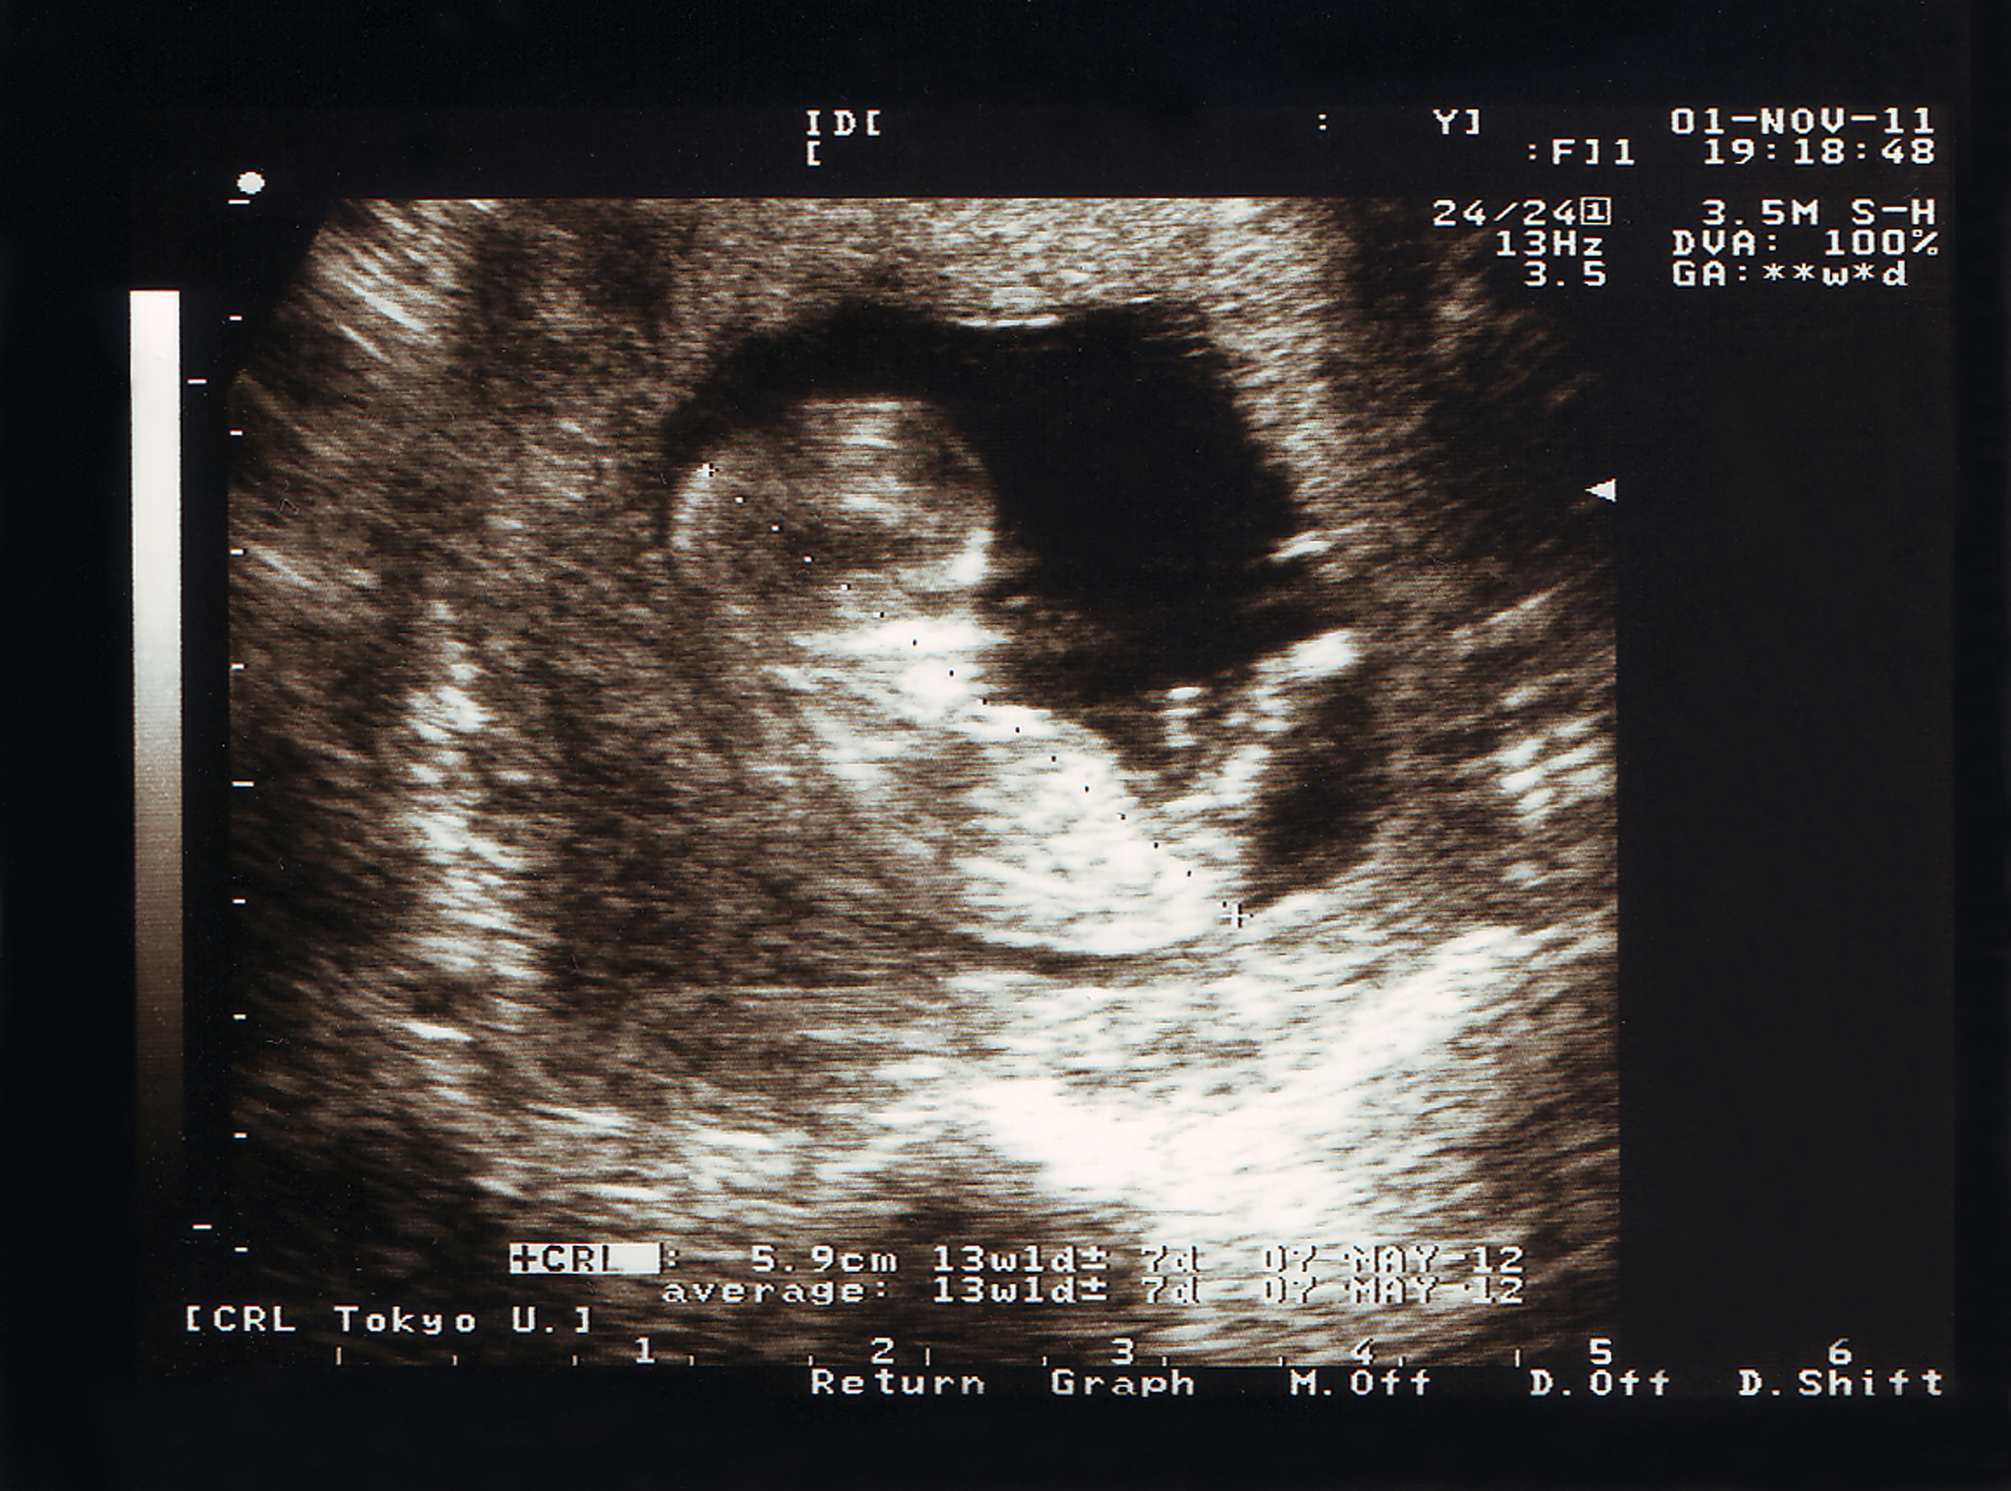

- Placenta and Amniotic Fluid: A portion of the weight contributes to the placenta and amniotic fluid, which protects and nourishes the baby.